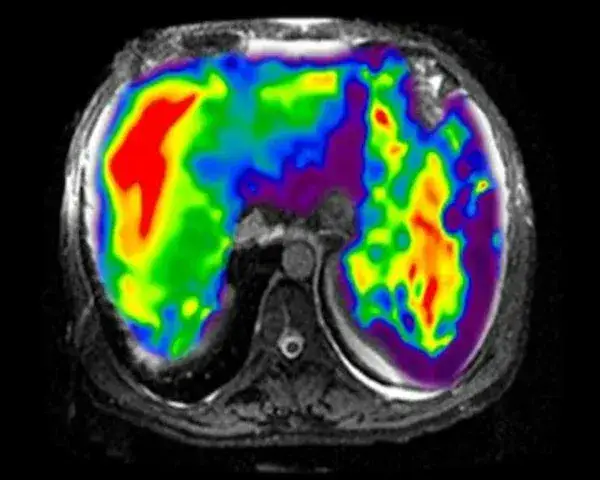

Podczas badania rezonansu magnetycznego pacjenci mogą oczekiwać komfortowego, choć specyficznego doświadczenia. Badanie zazwyczaj trwa od 20 do 60 minut, w zależności od obszaru ciała, który jest poddawany skanowaniu. Pacjent zostaje poproszony o leżenie nieruchomo na specjalnym stole, który wsuwa się do wnętrza dużego aparatu MRI. W trakcie badania może być słychać głośne dźwięki, które są normalne i pochodzą z pracy urządzenia. Warto również wiedzieć, że w niektórych przypadkach może być używany kontrast, który poprawia jakość obrazów, ale pacjent powinien być o tym wcześniej poinformowany.

Wyniki rezonansu magnetycznego mogą stanowić kluczowy element w planowaniu dalszej terapii pacjentów. Po przeprowadzeniu badania, lekarze mają dostęp do szczegółowych obrazów, które pomagają w diagnozowaniu schorzeń oraz monitorowaniu postępów w leczeniu. Dzięki nowoczesnym technikom analizy obrazów, specjalista może dokładniej określić, jakie terapie będą najbardziej skuteczne dla pacjenta, co może obejmować zarówno leczenie farmakologiczne, jak i fizjoterapię czy rehabilitację.